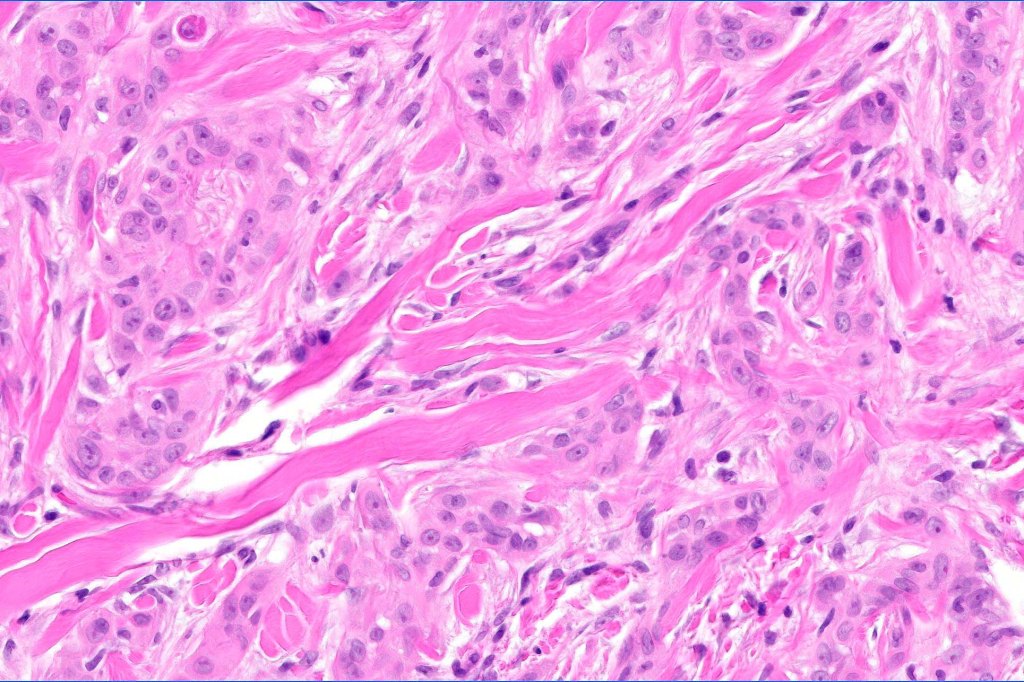

•Widely infiltrating biphasic tumor

•Perineural infiltration is commonly seen

•Microcystic adnexal carcinoma is sometimes confused with syringoid eccrine carcinoma. The former shows superficial keratocysts in the absence of SCC and in the deeper reaches, the epithelium is well differentiated & shows intracytoplasmic lumina and occasional well-formed ducts embedded in a dense fibrous stroma. Glands are not a feature